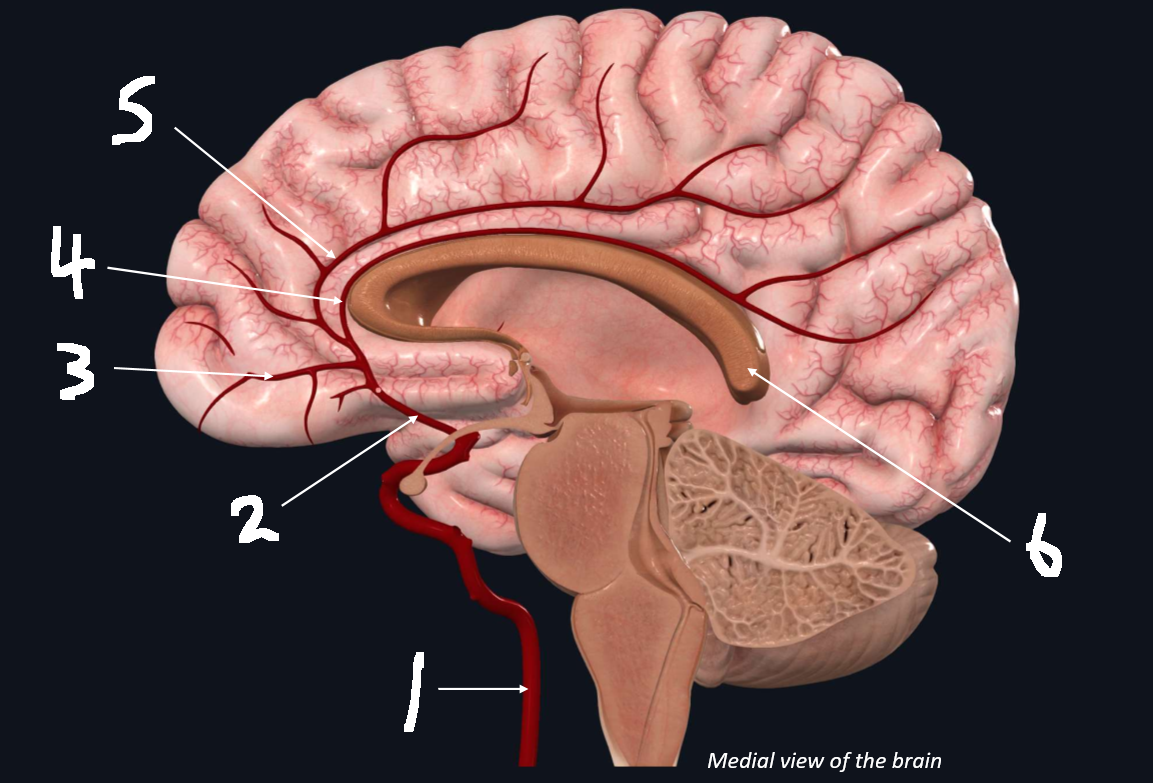

What is 1?

internal carotid artery

What is 2?

anterior cerebral artery

What is 3?

frontopolar artery

What is 4?

pericallosal artery

What is 5?

callosomarginal artery

What is 6?

corpus callosum